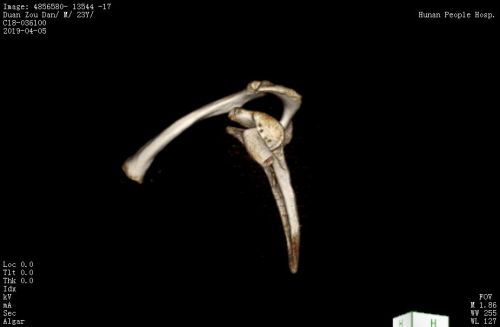

髂骨块的设计修整和打孔。

术后ct。

由于左肩脱位症状极重,患者入院当天早上再次发生脱位。CT检查发现,左肩胛盂有较大的骨缺损,缺损面积大约为15X35mm,相当于正常肩胛盂面积的30%。目前,针对此类肩胛盂(骨缺损>20%)修复,指南建议使用临近的喙突移植肩胛骨以修补骨性缺损(Lartarjet术),但不幸的是患者喙突发育不良,小于骨缺损体积,Lartarjet术没有条件实施。王靖果断决定利用髂骨来修复肩胛盂。该手术在关节镜下实施难度极大,是省内首次报道,同时也为肩关节脱位合并巨大肩胛盂缺损患者提供了肩关节镜微创治疗的新方法。术后复查CT可见左肩胛盂前方有一块移植髂骨块挡住了肱骨头脱位的轨迹。